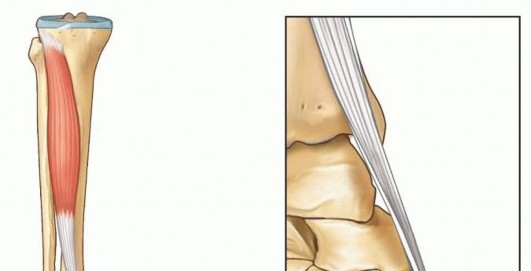

Illustration of anterior tibialis muscle - Dr. Mohammed Hutaif

Anterior Tibialis Transfer for Residual Clubfoot Deformity ## DEFINITION The incidence of residual deformity in congenital clubfoot ranges from 26.6% to 50%, regardless of the initial treatment provided. 2The disparity in the reported incidence is due to varying severity of clubfoot deformity, different methods of treatment, and, in part, differing definitions of residual deformity.Residual deformities include isolated equinus, cavus, metatarsus adductus, hindfoot varus, forefoot supination, and combinations of the above.Dynamic forefoot adduction and supination can be observed after clubfoot treatment with or without soft tissue releases.Dynamic forefoot supination deformity results from muscle imbalance. Anatomic imbalances can be due to primary absence or weakness of the anterior tibialis or peroneal muscles or as a result of neurologic abnormalities in the central nervous system or the peroneal nerve. Functional muscle imbalance can result from residual medial displacement of the navicular on the head of the talus. In this case, because its insertion is medially displaced, the anterior tibialis becomes a forefoot supinator instead of a dorsiflexor ( FIG 1). Illustration 1 for Why Anterior Tibialis Muscle Transfer Fixes Clubfoot --- Illustration 2 for Why Anterior Tibialis Muscle Transfer Fixes Clubfoot ### FIG 1 • Normal foot versus supinated foot. Medial subluxation of the navicular, the medial cuneiform, and the first metatarsal results in supination deformity as the line of pull of the tibialis anterior tendon directs the foot into supination instead of dorsiflexion. The aim of treatment is to correct any fixed deformity and to rebalance the muscles of the foot, thereby correcting dynamic deformity and improving foot alignment. ## ANATOMY The anterior tibialis muscle originates from the upper two-thirds of the tibia.The anterior tibialis tendon fibers rotate 90 degrees from the musculotendinous junction to its insertion on the medial cuneiform and first metatarsal.Medial rotation begins proximally, so the most medial muscle fibers proximally rotate to the posterior surface of the tendon near the midpoint and continue to rotate so that their final insertion is as the distal-lateral fibers on the first metatarsal.Meanwhile, the most lateral muscle fibers proximally rotate to the anterior surface at the midpoint andcontinue distally to insert on the cuneiform as the proximal-medial fibers ( FIG 2).4 Illustration 3 for Why Anterior Tibialis Muscle Transfer Fixes Clubfoot --- Illustration 4 for Why Anterior Tibialis Muscle Transfer Fixes Clubfoot ### FIG 2 • Anatomy of the tibialis anterior muscle-tendon. The anterior tibialis tendon fibers rotate 90 degrees from their musculotendinous junction to their insertion on the medial cuneiform and the first metatarsal such that the proximal-medial insertional fibers on the cuneiform begin as the lateral fibers at the musculotendinous junction (see window).